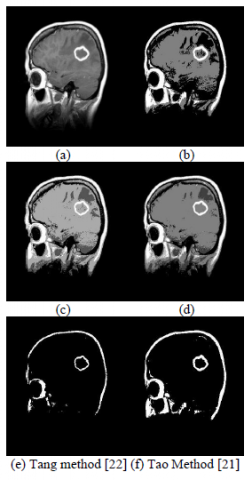

We have compared our method with similar existing techniques based on qualitative evaluation. For that, the first original image of human brain and their corresponding qualitative results have been shown in Figure 2 (a), where level 2, level 3, and level 4 of threshold-based segmentation results of our approach have been shown in Figure 2 (b), (c), and (d) respectively. The experimental results for Tao et al, method [21] and Tang method [22] have been shown in Figure 2 (e) and (f) respectively. It has been clearly visible from the results obtained through our approach make the cerebral cortex outstanding i.e., perform better segmentation than other techniques. In the similar way, Lung image’s results have been shown in Figure 3, where original image has been shown in Figure 3 (a), level 2, level 3, and level 4 of threshold-based segmentation results for our proposed technique have been shown in Figure 3 (b), (c), and (d) respectively. The results of Tao et al., method [21] and Tang method [22] have been shown in Figure 3 (e) and (f) respectively. Again, it has been evident from the results that segmentation performance of our technique is far better than compared approaches. The results with the third image “Liver” have been shown in Figure 4, where original image has been shown in Figure 4 (a), and level 2 level 3, and level 4 threshold-based segmentation results of our approach have been shown in Figure 4 (b), (c), and (d) respectively. Tao et al., [21] and Tang [22] results on Liver image have been displayed in figure 4(e) and (f) respectively. The results with the fourth image have been shown in Figure 5, where original image has been shown in Figure 5 (a), and level 2 level 3, and level 4 threshold-based segmentation results of our approach have been shown in Figure 5 (b), (c), and (d) respectively. Tao et al., [21] and Tang [22] results on Liver image have been displayed in Figure 5(e) and (f) respectively. It is evident from experiment results and qualitative performance analysis that our algorithm outperforms existing methods especially in case of low contrast image.

Figure 2. Results with human brain image